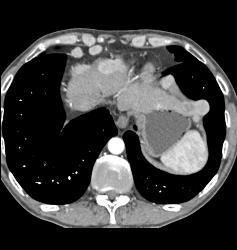

Para-cardiac Nodes in A Carcinoid Patient